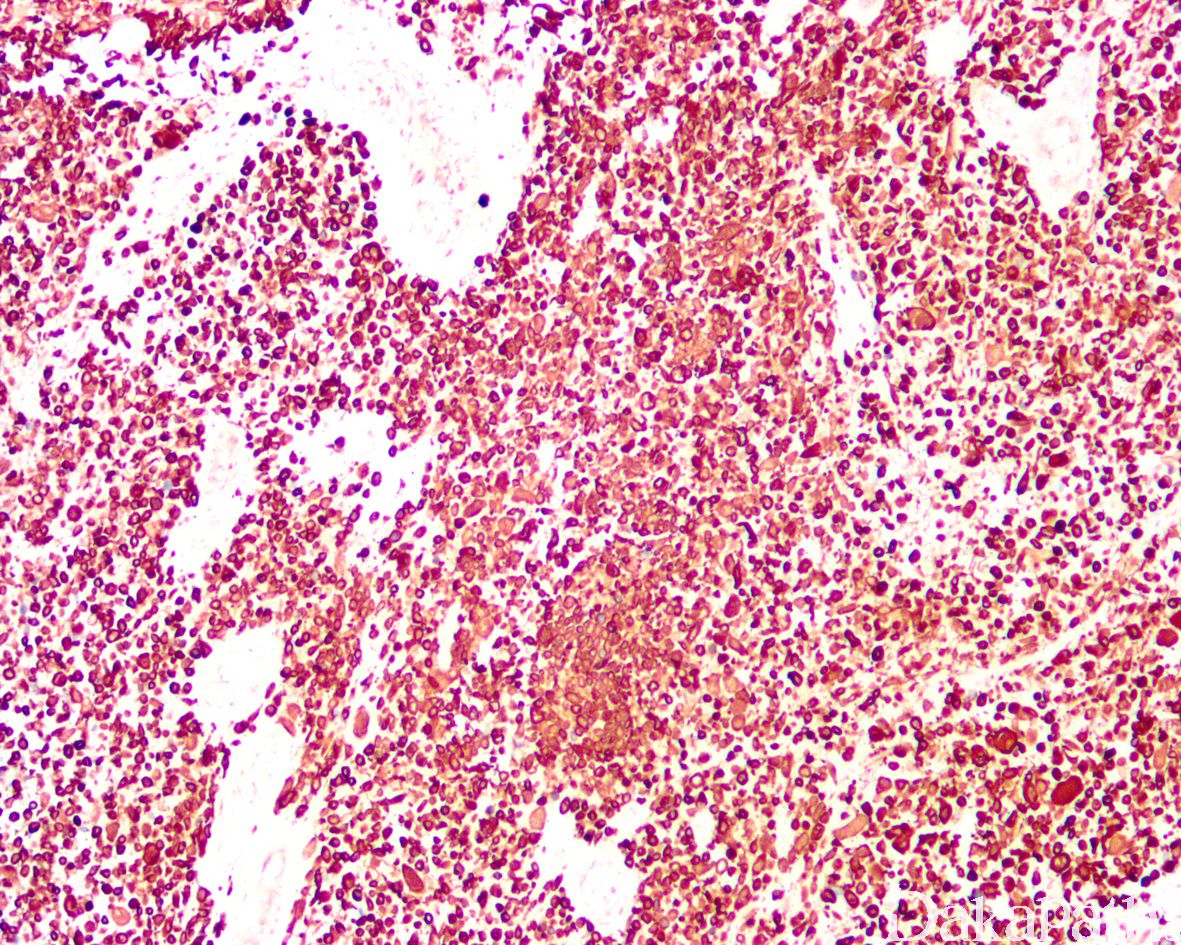

浆细胞样尿路上皮癌与普通的尿路上皮癌具有相似的免疫表型特征表达 GATA3(80%),P63(45%),CK7( 92%),CK20(70%)。由于 CDH1 基因突变,浆细胞样尿路上皮癌常出现 E-cadherin 表达缺失。少数可表达 GCDFP15,PR,CDX2 等。部分可表达 CD128,需要与浆细胞瘤鉴别,但不表达 CD38 和 MUM1 等浆细胞标志物。